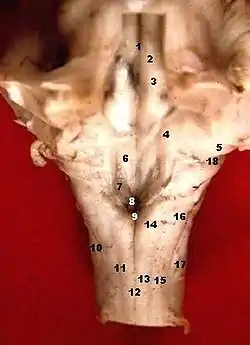

![]() Human caudal brainstem posterior view (The sulcus limitans separates #2 from #4.) | |

The sulcus limitans is a groove on either side of the midline in the rhomboid fossa (floor of the fourth ventricle).[1] It separates the cranial nerve motor nuclei (located medial), and the sensory nuclei (located lateral).[2][1] It is parallel to the median sulcus.